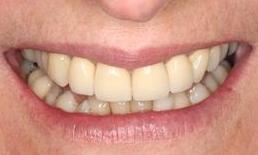

The patient wanted to be able to smile when she retires and travels around. An infected upper incisor was removed before a carefully designed ceramic bridge and a crown were placed. She was so thrilled with the result! Now she can show her teeth when she smiles in her photos.